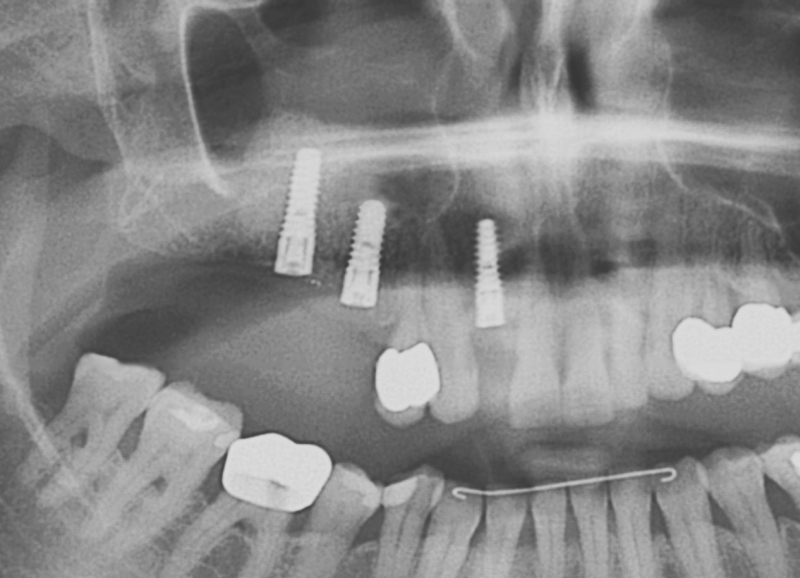

11/20 - Detail of OPG showing radiopacity of maxresorb®GBR with maxresorb® & Jason® membrane - Prof. Dr. Dr. D. Rothamel